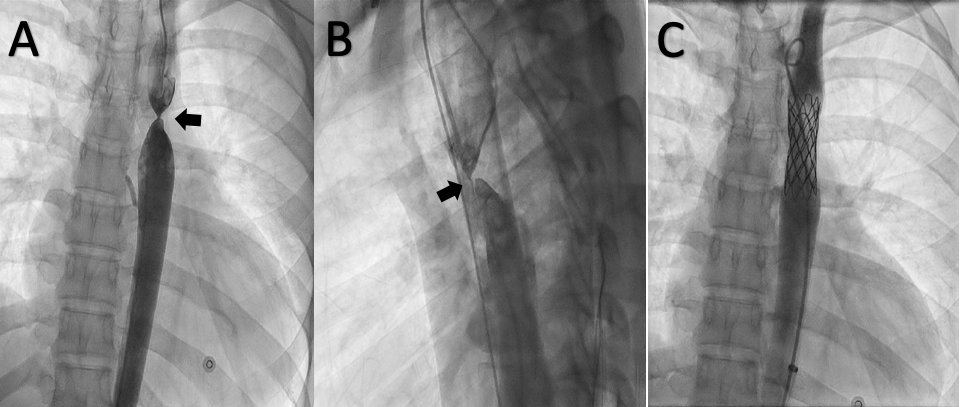

Simultaneous antegrade and retrograde aortogram showed complete occlusion with no communication between the 2 segments, suggestive of functional aortic atresia (Figure, A & B; Video 1). A Mullins dilator (Medtronic) was parked in the distal segment of the CoA. A Brockenbrough needle (Medtronic) was taken to the distal end of the Mullins dilator. The hard end of a 0.014-inch Runthrough wire (Terumo) was passed through the Brockenbrough needle and perforated the atretic segment, which was confirmed by an angiogram in the proximal segment in 2 orthogonal views (Videos 2, 3). The atretic segment was punctured with the Brockenbrough needle over the 0.014-inch wire.

Later, the Mullins dilator was pushed across the atresia and contrast was injected through it to confirm the position. The CoA segment was dilated with an 8 x 30-mm Tyshak II balloon (NuMED) and the 7-F RFA sheath was upgraded to a 14-Fr Mullins sheath after predilating with 10- and 12-Fr dilators (Video 4). A 4.5 x 8-mm zig-covered Cheatham-Platinum (CP) stent (NuMED) was crimped over a 5 cm x 15-mm Z MED II balloon (B. Braun), and the stent was deployed at 8 atm across the CoA segment (Video 5). The post-stent deployment angiogram showed no narrowing across the CoA segment and no leak (Figure, C; Video 6). The gradient across the CoA segment disappeared completely. The patient was off antihypertensives and doing well at 2-month follow-up.